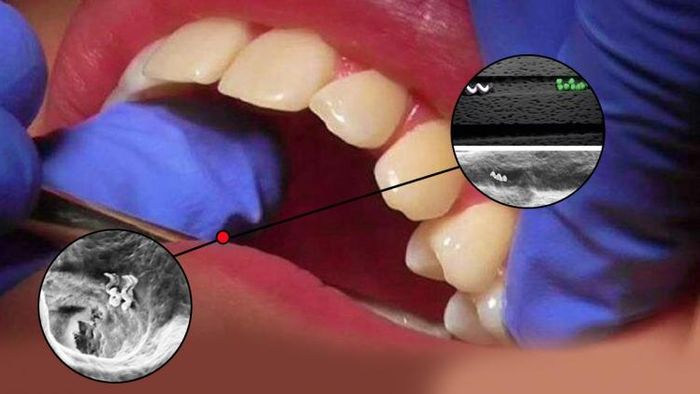

তিনি এবং তাঁর ইন্ডিয়ান ইন্সটিটিউট অফ সায়েন্স (আইআইএসসি)-এর ছাত্রদের তৈরি স্টার্ট-আপ থেরানটিলাস সফলভাবে প্রমাণ করেছে চৌম্বকীয় ক্ষেত্র ব্যবহারে ন্যানোরো-আকারের রোবোর সাহায্যে দাঁতের নালির অতি গভীরে থাকা ব্যাকটেরিয়া মেরে ফেলা যায় এবং রুট ক্যানাল চিকিৎসায় এটিকে সফলভাবে প্রয়োগ করা যেতে পারে।

‘অ্যাডভান্সড হেলথকেয়ার মেটিরিয়ালস’-এ প্রকাশিত সমীক্ষায় গবেষকরা দেখিয়েছেন লোহার প্রলেপ দেওয়া সিলিকন ডাই অক্সাইড দিয়ে তৈরি হেলিকাল ন্যানোরোবট নিয়ন্ত্রণ করা যেতে পারে। একটি সূক্ষ্ম যন্ত্রের মাধ্যমে যেটা কম ক্ষমতা সম্পন্ন চৌম্বকীয় ক্ষেত্র সৃষ্টি করে। এই ন্যানোরোবটগুলিকে এরপর তুলে ফেলা দাঁতের নমুনায় ঢুকিয়ে দেওয়া হয় এবং এরপর ওই ন্যানোরোবটগুলির চলাচলে নজর রাখা হয় অনুবীক্ষণ যন্ত্রের সাহায্যে।

গবেষকদের ওই দলটি চৌম্বকীয় ক্ষেত্র নিয়ন্ত্রঁ করার ওপর জোর দেন। যাতে ন্যানোরোবটগুলির পৃষ্ঠতল তাপ উৎপাদন করতে সমর্থ হয়। যা জীবাণু মারতে সাহায্য করে। চৌম্বকীয় ক্ষেত্রের কম্পাঙ্ক নির্ধারণ করে গবেষকদল ন্যানোরোবটের চলাচল দাঁতের নালির অত্যন্ত গভীরে যাতে প্রবেশ করতে পারে, সে ব্যাপারে জোর হন।